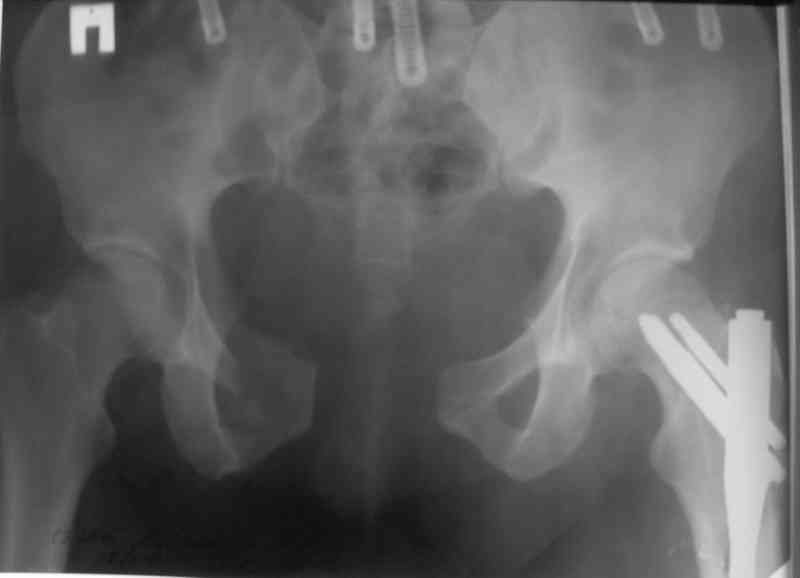

Вчера прооперировал больного.

Попытка низвести половину таза на тракционном столе ( скелетное вытяжение за бедро) безуспешная.

из переднего доступа добрался до правого КП сочленения , все запаяно костью, с помощью 2 шанцев винтов в крестец и подвздошную кость и элеватора репозиция, контроль ЭОП

и двумя пластинами фиксация.

Спереди, аппарат как рекомендовал Джолдас.

Снимки плохого качества( очень темные) завтра переделают и пришлю на конференцию.

На мой взгляд, смещение устранено и фиксация выглядит вполне анатомичной.

В приложении послеоперационные картинки.